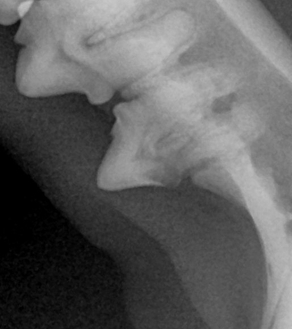

덴탈 X-ray를 통해 치아 내부 상태를 정확히 파악한 후, 아이에게 불필요한 고통 없이 최선의 결정을 내릴 수 있도록 안내합니다.

BEFORE

AFTER